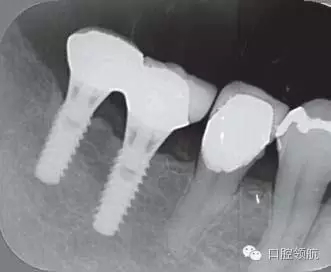

修復(fù)體安裝后的2003年1月復(fù)診時的X線片上,沒有發(fā)現(xiàn)種植體頸部有骨吸收現(xiàn)象,情況良好(圖2)。但是,2003年8月,因混合陶瓷樹脂部分修復(fù)體的破損而進(jìn)行再制作時,發(fā)現(xiàn)有輕度的咬合疼痛以及舌側(cè)頸部的牙齦有輕壓痛??趦?nèi)沒有觀察到該部位的牙齦紅腫。X線片可以觀察到(左下第6顆牙) 的種植體頸部有達(dá)到第4螺紋的骨吸收現(xiàn)象(圖3)。

圖3(左下第6顆牙)的種植體的骨吸收達(dá)到第4螺紋(2003年8月)